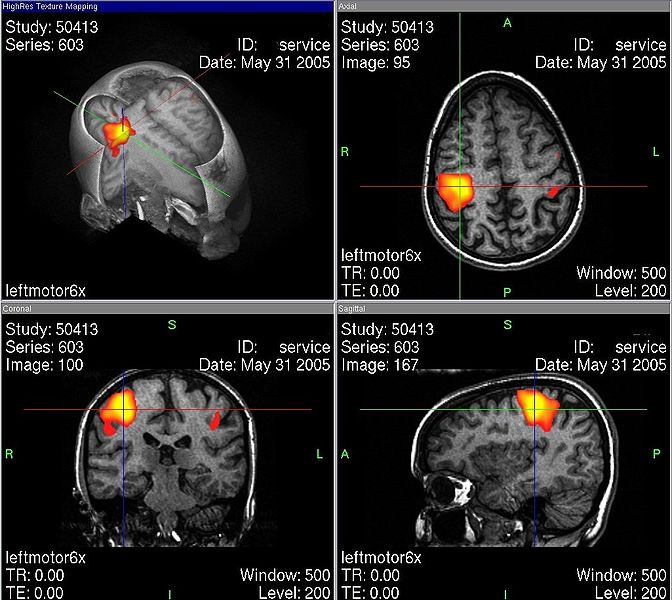

Integran hallazgos de diferentes aproximaciones, determina qué estímulos hacen que las células respondan; utilizan técnicas de neuroimagen para ubicar las regiones exactas de activación cerebral durante una tarea; obtienen información, principios y construyen modelos de cómo se llevan a cabo las operaciones mentales en el cerebro.

Neuroimagen del cerebro realizando diferentes tareas